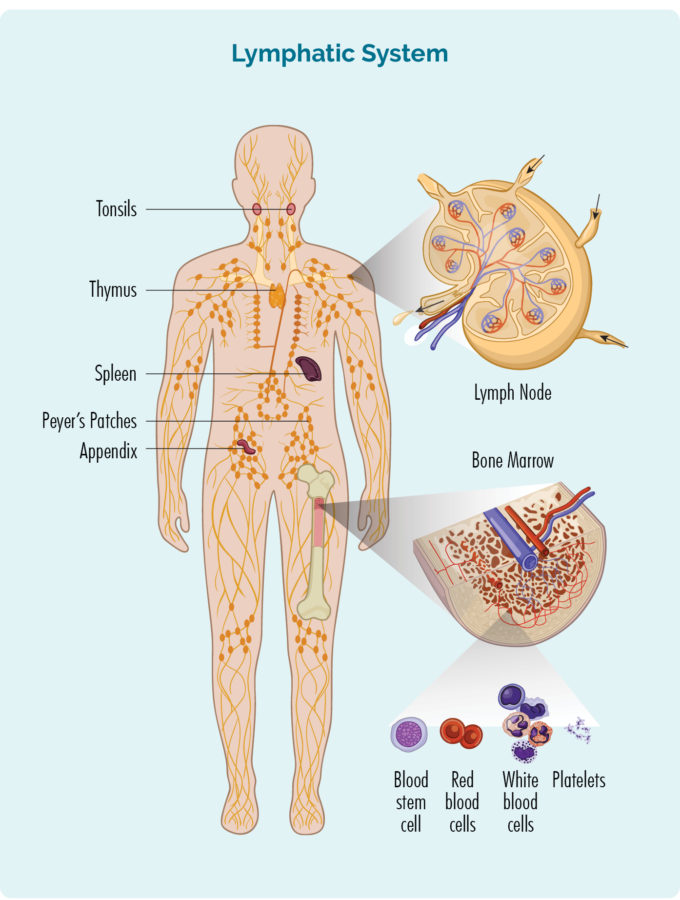

There are different things that can increase your risk of developing AVN. Some may be related to your lymphoma, and some may be completely unrelated to your lymphoma. See the list below for lymphoma related, and non-cancer related causes of AVN.

- Long-term use of high-dose corticosteroids

- Chemotherapy

- Certain medical treatments like bone marrow biopsy or bone grafting.